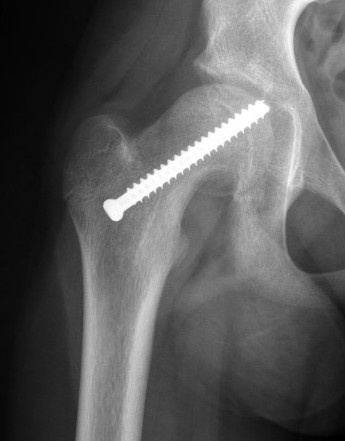

Subtrochanteric fracture

Subtrochanteric fracture likely causes by multiple drill holes / attempts

Cause

Too low screw entry

Multiple drill holes to get correct entry

Management

Intramedullary nail